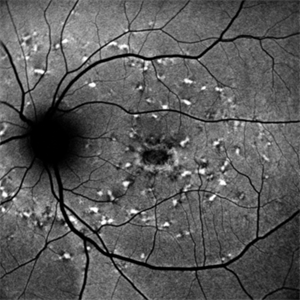

Stargardt's Disease

Stargardt's Disease

Oct 4 2018 by Aditya S Kelkar, MS, FRCS, FASRS,FRCOphth

Auto-fluorescence image of a 19-year-old male showing flecks of both increased and decreased autofluorescence and reduced central macular autofluorescence surrounded by an increased signal.

Photographer: Dr. Aanchal Agarwal

Condition/keywords: Stargardt disease